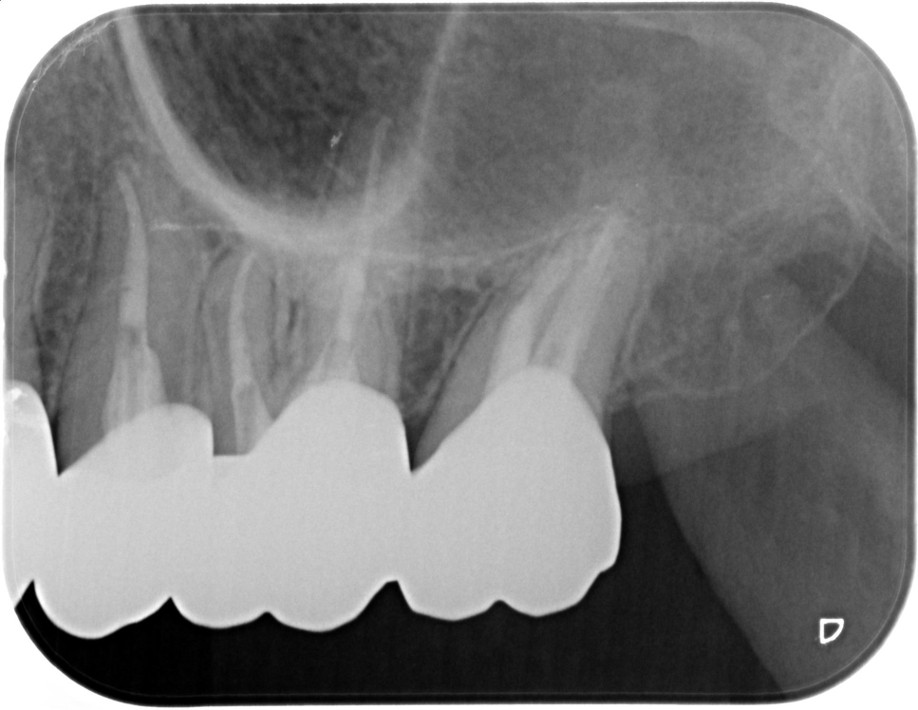

| 患者様データ | 60代 男性 |

| 来院時の主訴 | 「右下の歯が噛むと痛い。」 |

| 医院の診断 | セメント質剥離を併発した歯根破折 |

| 治療費 | 総額:270,000円(税抜) 【内訳】 精密根管治療80,000円+歯牙再植100,000円、ファイバーポストコア20,000円、ダイレクトボンディング治療70,000円 |

すでに歯根破折を起こしている歯のため、かなりシビアな状態ではありますが、患者様の強い要望により歯牙再植を応用した方法により歯の保存を行いました。 |